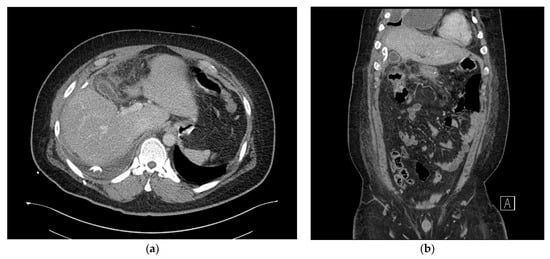

A 29-year-old man (136.5 kg, 186.0 cm, body mass index (BMI) 39.3 kg/m2) was admitted for bariatric surgery. The patient had a history of treatment for paranoid schizophrenia 10 years ago and severe sleep apnea, as well as a surgical history of septoplasty for sleep apnea. Social and familial histories were non-specific. Furthermore, the patient had no history of diseases or medication that could potentially cause immunosuppression. Preoperative chest posteroanterior (PA), gastroduodenoscopy, abdominal computed tomography (CT), and laboratory testing were carried out 2 weeks before surgery. The patient had no history of gallbladder stones, but due to limitations in physical examination and abdominal ultrasonography caused by obesity, an abdominal computed tomography (CT) scan was performed to differentiate gallbladder stones. No remarkable abnormal findings were observed on endoscopy and chest PA. Additionally, no evidence of hepatic mass and perihepatic abscess or inflammation was observed on the CT, apart from severe fatty liver findings (Figure 1a,b). In March 2020, a laparoscopic sleeve gastrectomy was performed with no intra-operative complications, and the surgical site was not irrigated. Routine prophylactic administration of 1st-generation cephalosporin was given before surgery and within 24 h after surgery.

Figure 1. (a) Axial view of the abdominal computed tomography (CT) scan and (b) coronal view of the abdominal computed tomography (CT) scan showing no evidence of hepatic mass or perihepatic inflammation.